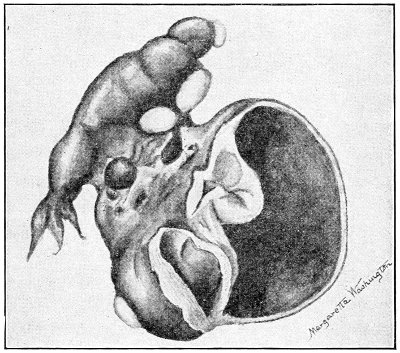

The origin of vaginal cysts has been much disputed. It is probable that they arise from the remains of the Wolffian canal—the canal of Gärtner. In the embryo the transverse or longitudinal tubule of the parovarium extends to the side of the uterus and thence down the side of the vagina to the urethral orifice. It persists in this condition in some of the lower animals—the sow and the cow—and may also persist as a closed tube in woman. In such cases it may become distended and form the vaginal cyst.

The symptoms of this condition are due to retention of the uterine discharges. There is no discharge of 53 menstrual blood from the vagina. Attacks of pain occur periodically at the menstrual periods. A cystic tumor, which may be felt by rectal examination, is present. The tumor consists of the distended portion of the vaginal canal (hematocolpos), and sometimes of the distended cervical canal and body of the uterus. The contents of the hematocolpos are usually sterile, although they may become purulent (pyocolpos).